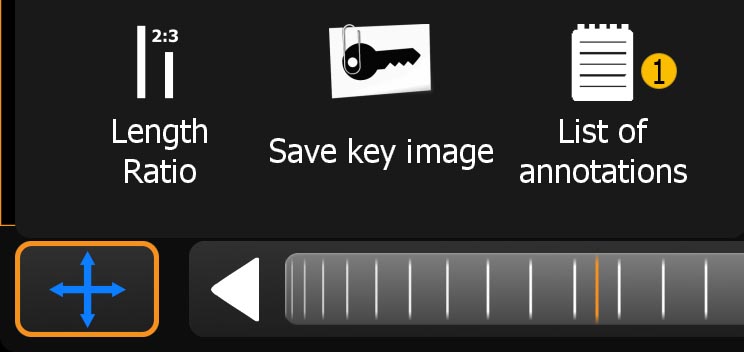

-

Length ratio: Show the length ratio between two lines.

-

Segmentation: Create a manual segmentation.

-

Save keyimage (to PACS): Saves the current view with all Annotations. The original dataset will not be touched. Optionally the keyimage will be uploaded to the PACS if your license supports the 'PACS upload' and it is properly configured.

-

Save Hanging: Save actual slices position and orientation from all view for future use.

-

List of annotations: Contains all annotations you added to the image. By long pressing an annotation in the list, more options such as multi-select, rename and delete will appear.

11.1.2. Annotation menu

The following button (see List of annotations) will appear in the Toolmenu if the user has created any annotations.

-

Opens the 'List of annotations' window

-

A single tap selects and jumps to the annotation. Tap and hold will open the annotation submenu (Item 2,3).

-

Deletes the selected annotation.

-

Edit the name of the currently selected annotation.